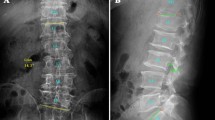

Anteroposterior whole spine or EOS radiographs were obtained with the patient in the standing position. These images were used to measure the Cobb angle, coronal imbalance, pelvic height and angle, and femoral head height. Coronal imbalance was defined as the horizontal distance between the C7 plumb line and the center sacral vertical line in the coronal plane. Pelvic height and angle were defined as the vertical distance and angle between the upper borders of both iliac crests, respectively. Femur head height was defined as the vertical distance between the upper borders of both femur heads (Fig. 1). Pelvic height and femoral head height on standing PA radiographs or EOS radiographs are a simple and reliable method for LLD documentation with an average magnification of 4.6%14,15.

Figure (A) shows how we measured the Cobb angle (a) and coronal imbalance (b). Coronal imbalance was defined as the horizontal distance between the C7 plumb line and the center sacral vertical line in coronal plane. Figure (B) shows how we measured pelvic height (a) and angle (b), and femoral head height (c). Pelvic height and angle were defined as the vertical distance and angle between bilateral upper border of iliac crest. Femur head height was defined as the vertical distance between the upper borders of both femur heads.